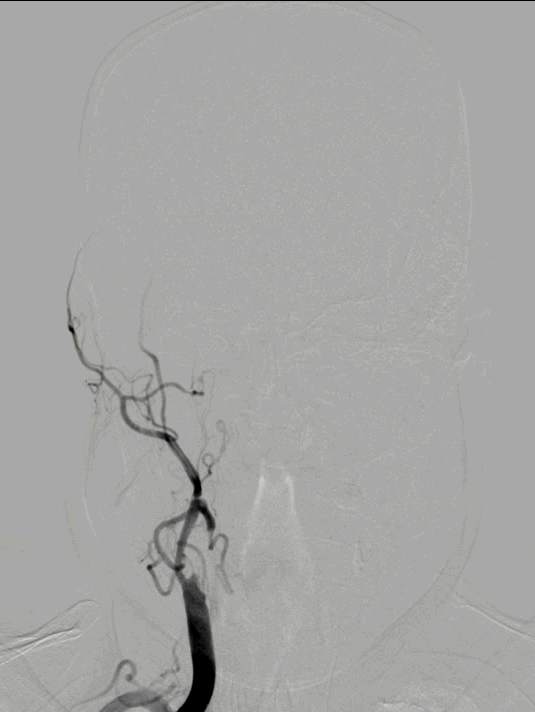

脑血管造影:3型主动脉弓,右侧颈内动脉起始段闭塞,后循环及左侧颈内动脉均未向左侧颈内动脉供血区代偿。

3型主动脉弓,用Mani管超选至右颈总动脉,用260cm加硬泥鳅导丝交换出,在泥鳅导丝导引下,用125cm的多功能管将6F Infinity长鞘置于右颈总动脉,提供稳定支撑。

RICA C1闭塞,来自RACA丰富的软膜支代偿。

RVA超选造影仍可见后循环丰富的软膜支向右侧颞叶代偿供血。

FlowGate 2同轴Catalyst 7、Synchro 2多次调整后穿过C1起始闭塞处,MicroPort Pioneer 2.5mm×20mm球囊C1起始处缓慢扩张,顺球囊Catalyst 7穿过闭塞段,继续向前推进FlowGate 2失败, Catalyst 7 C1抽吸出长条血栓。